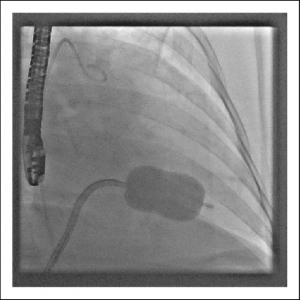

کارگزاری فیلتر IVC

فیلتر وناکاوا (IVC Filter)